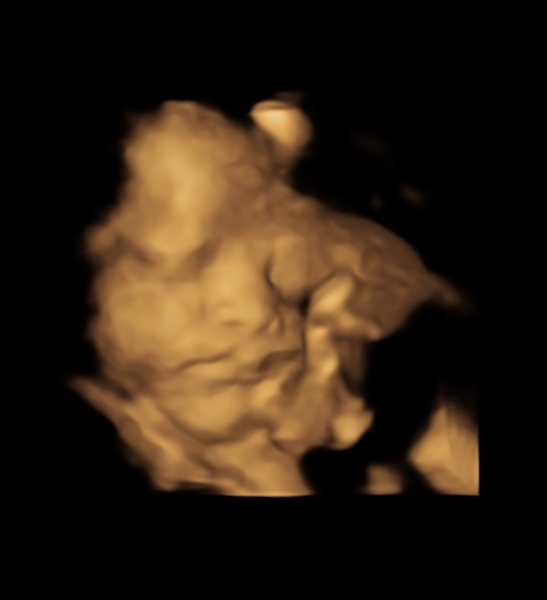

Just been for a private growth scan and got some cute images 😍

@jpaws ahhh very cute!

@jpaws beautiful 😍

Lovely pic there 😃. Xx